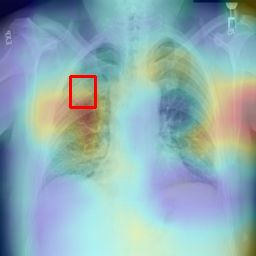

Deployments of artificial intelligence in medical diagnostics mandate not just accuracy and efficacy but also trust, emphasizing the need for explainability in machine decisions. The recent trend in automated medical image diagnostics leans towards the deployment of Transformer-based architectures, credited to their impressive capabilities. Since the self-attention feature of transformers contributes towards identifying crucial regions during the classification process, they enhance the trustability of the methods. However, the complex intricacies of these attention mechanisms may fall short of effectively pinpointing the regions of interest directly influencing AI decisions. Our research endeavors to innovate a unique attention block that underscores the correlation between 'regions' rather than 'pixels'. To address this challenge, we introduce an innovative system grounded in prototype learning, featuring an advanced self-attention mechanism that goes beyond conventional ad-hoc visual explanation techniques by offering comprehensible visual insights. A combined quantitative and qualitative methodological approach was used to demonstrate the effectiveness of the proposed method on the large-scale NIH chest X-ray dataset. Experimental results showed that our proposed method offers a promising direction for explainability, which can lead to the development of more trustable systems, which can facilitate easier and rapid adoption of such technology into routine clinics. The code is available at www.github.com/NUBagcilab/r2r_proto.